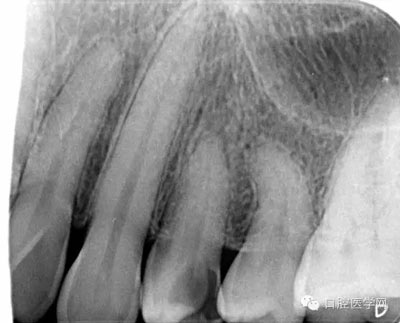

第一步:拍攝X線片,觀察髓腔形態(tài)以及根管走向,疑似根管長度較短且彎曲。

檢查:24遠(yuǎn)中鄰合面見一黃豆大小齲洞,探及穿髓孔,叩(-),松動(-),冷熱診劇烈疼痛,牙齦正常。